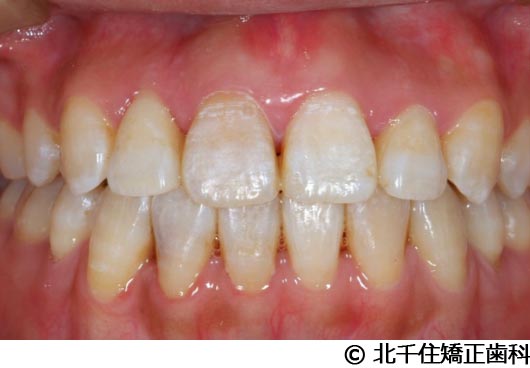

【症例3】叢生

- 治療前

- 治療後

- 治療名

- 叢生

- 費用

- 1,125,000円(税込)

- 期間

- 2年1ヵ月

- 治療回数

- 26回

- 通院頻度

- 1ヵ月ごと

- 年齢・性別

- 19歳3ヵ月・女性(初診時)

治療内容

-

患者様の症状

主訴:デコボコ、口元の突出

治療方法

上下顎第一小臼歯4本を抜歯してワイヤー矯正(セラミックブラケット)。

治療結果

叢生に対し抜歯を併用した矯正治療により、歯列および咬合関係の調整を行った症例である。治療後は保定装置を使用し、歯列および咬合の安定維持を目的として定期的な経過観察を行っている。

※治療結果は個人差があります。

治療を行う上での注意点(リスク・副作用)

歯磨き不良に伴うカリエスや歯周病、歯根吸収など。